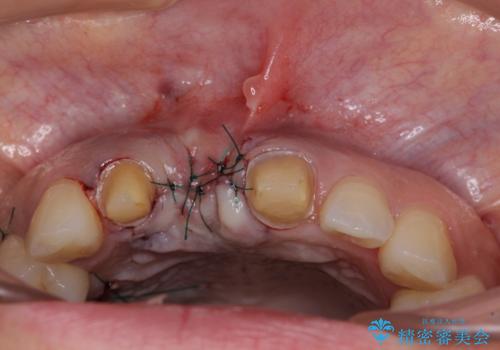

抜歯後は歯肉が痩せてしまうため、歯肉移植を行って歯肉の形態を改善した後、オールセラミックブリッジにて補綴することとしました。

- 外科手術のため、術後に痛みや腫れ、違和感を伴います